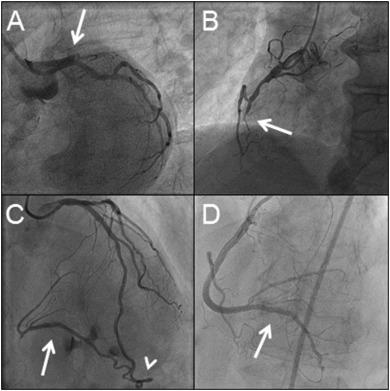

تشخیص قطعی CTO از طریق آنژیوگرافی عروق کرونر انجام میشود.

در آنژیوگرافی مشخص میشود:

باز کردن CTO نیازمند تکنیکهای پیشرفته و ابزارهای خاص است که بسته به آناتومی رگ انتخاب میشوند:

در نهایت، پس از عبور موفق، آنژیوپلاستی و استنتگذاری انجام میشود.